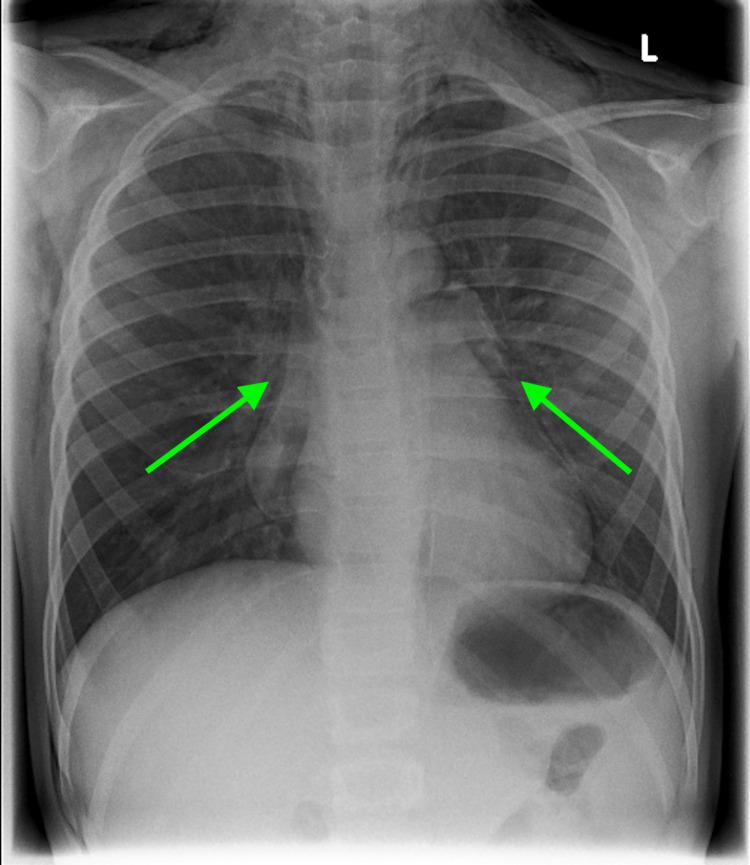

Tracheal lacerations in the paediatric population are not common; however, they can be life-threatening. Prompt diagnosis and management are essential for a good prognosis. Here, we present the case of a nine-year-old boy who presented to the hospital following a bicycle handlebar injury with neck pain and subcutaneous emphysema of the anterior thorax and neck. Chest X-ray revealed pneumomediastinum and a small pneumothorax. A computed tomography scan revealed a posterior longitudinal laceration of the trachea, measuring 1.5 cm, located superior to the carina at T1/2. As the patient was clinically stable, did not require any supplemental oxygen, and the tear was smaller than 2 cm, conservative management with steroids and broad-spectrum antibiotics was implemented. The patient was transferred to a tertiary ENT centre in Glasgow for observation in the paediatric intensive care unit where he recovered uneventfully. A repeat cross-sectional imaging six days after the injury revealed successful healing of the laceration. Non-surgical management of a tracheobronchial injury can be an effective approach. This can be considered in the case of tears measuring <2 cm and in clinically stable patients. Imaging-based diagnosis in the case of patients with minor injuries who are improving with conservative treatment may be sufficient, and confirmation with bronchoscopy would be of questionable clinical value in such patients.

小儿气管撕裂伤并不常见;然而,它们可能危及生命。及时诊断和处理对于良好的预后至关重要。在此,我们报告一例9岁男孩的病例,该男孩因自行车车把损伤后出现颈部疼痛以及前胸和颈部皮下气肿而入院。胸部X线显示纵隔气肿和小气胸。计算机断层扫描显示气管后纵行撕裂伤,长1.5 cm,位于T1/2水平的隆突上方。由于患者临床稳定,无需任何补充氧气,且撕裂伤小于2 cm,因此实施了使用类固醇和广谱抗生素的保守治疗。患者被转至格拉斯哥的一家三级耳鼻喉中心,在儿科重症监护病房接受观察,他恢复顺利。受伤6天后的重复横断面成像显示撕裂伤已成功愈合。气管支气管损伤的非手术治疗可能是一种有效的方法。对于长度<2 cm的撕裂伤以及临床稳定的患者可考虑采用这种方法。对于伤势较轻且经保守治疗病情好转的患者,基于影像学的诊断可能就足够了,在此类患者中行支气管镜检查以确诊的临床价值存疑。